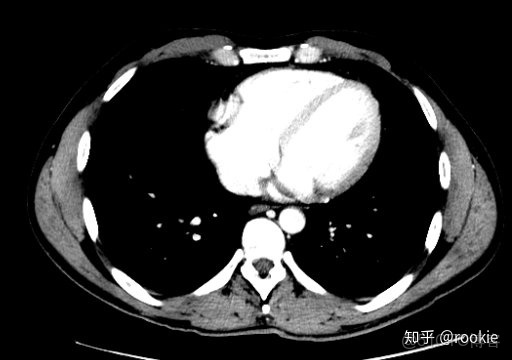

縱隔窗口窗口設置: (W:500,L:50)優點: 這些設置在本質上與軟組織設置或腹部設置相似,並進行了微調,以儘可能清晰地顯示出縱隔病理。

CLAHE算法增強局部對比度的X光圖像增強效果對比_#python 計算對比度_13

縱隔窗與腹部或軟組織窗相似,但稍作調整以顯示縱隔結構。